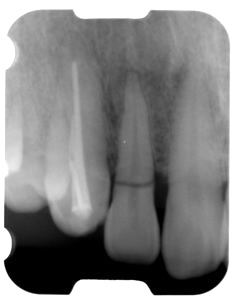

術後(レントゲン)、左下奥2本インプラント